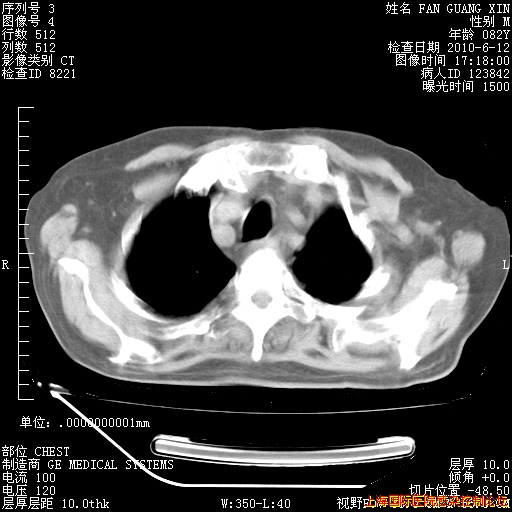

6月12日纵膈窗

回复

整整相隔30天的肺部CT好像有所好转啊。甲强龙减量第3天,需要观察体温。